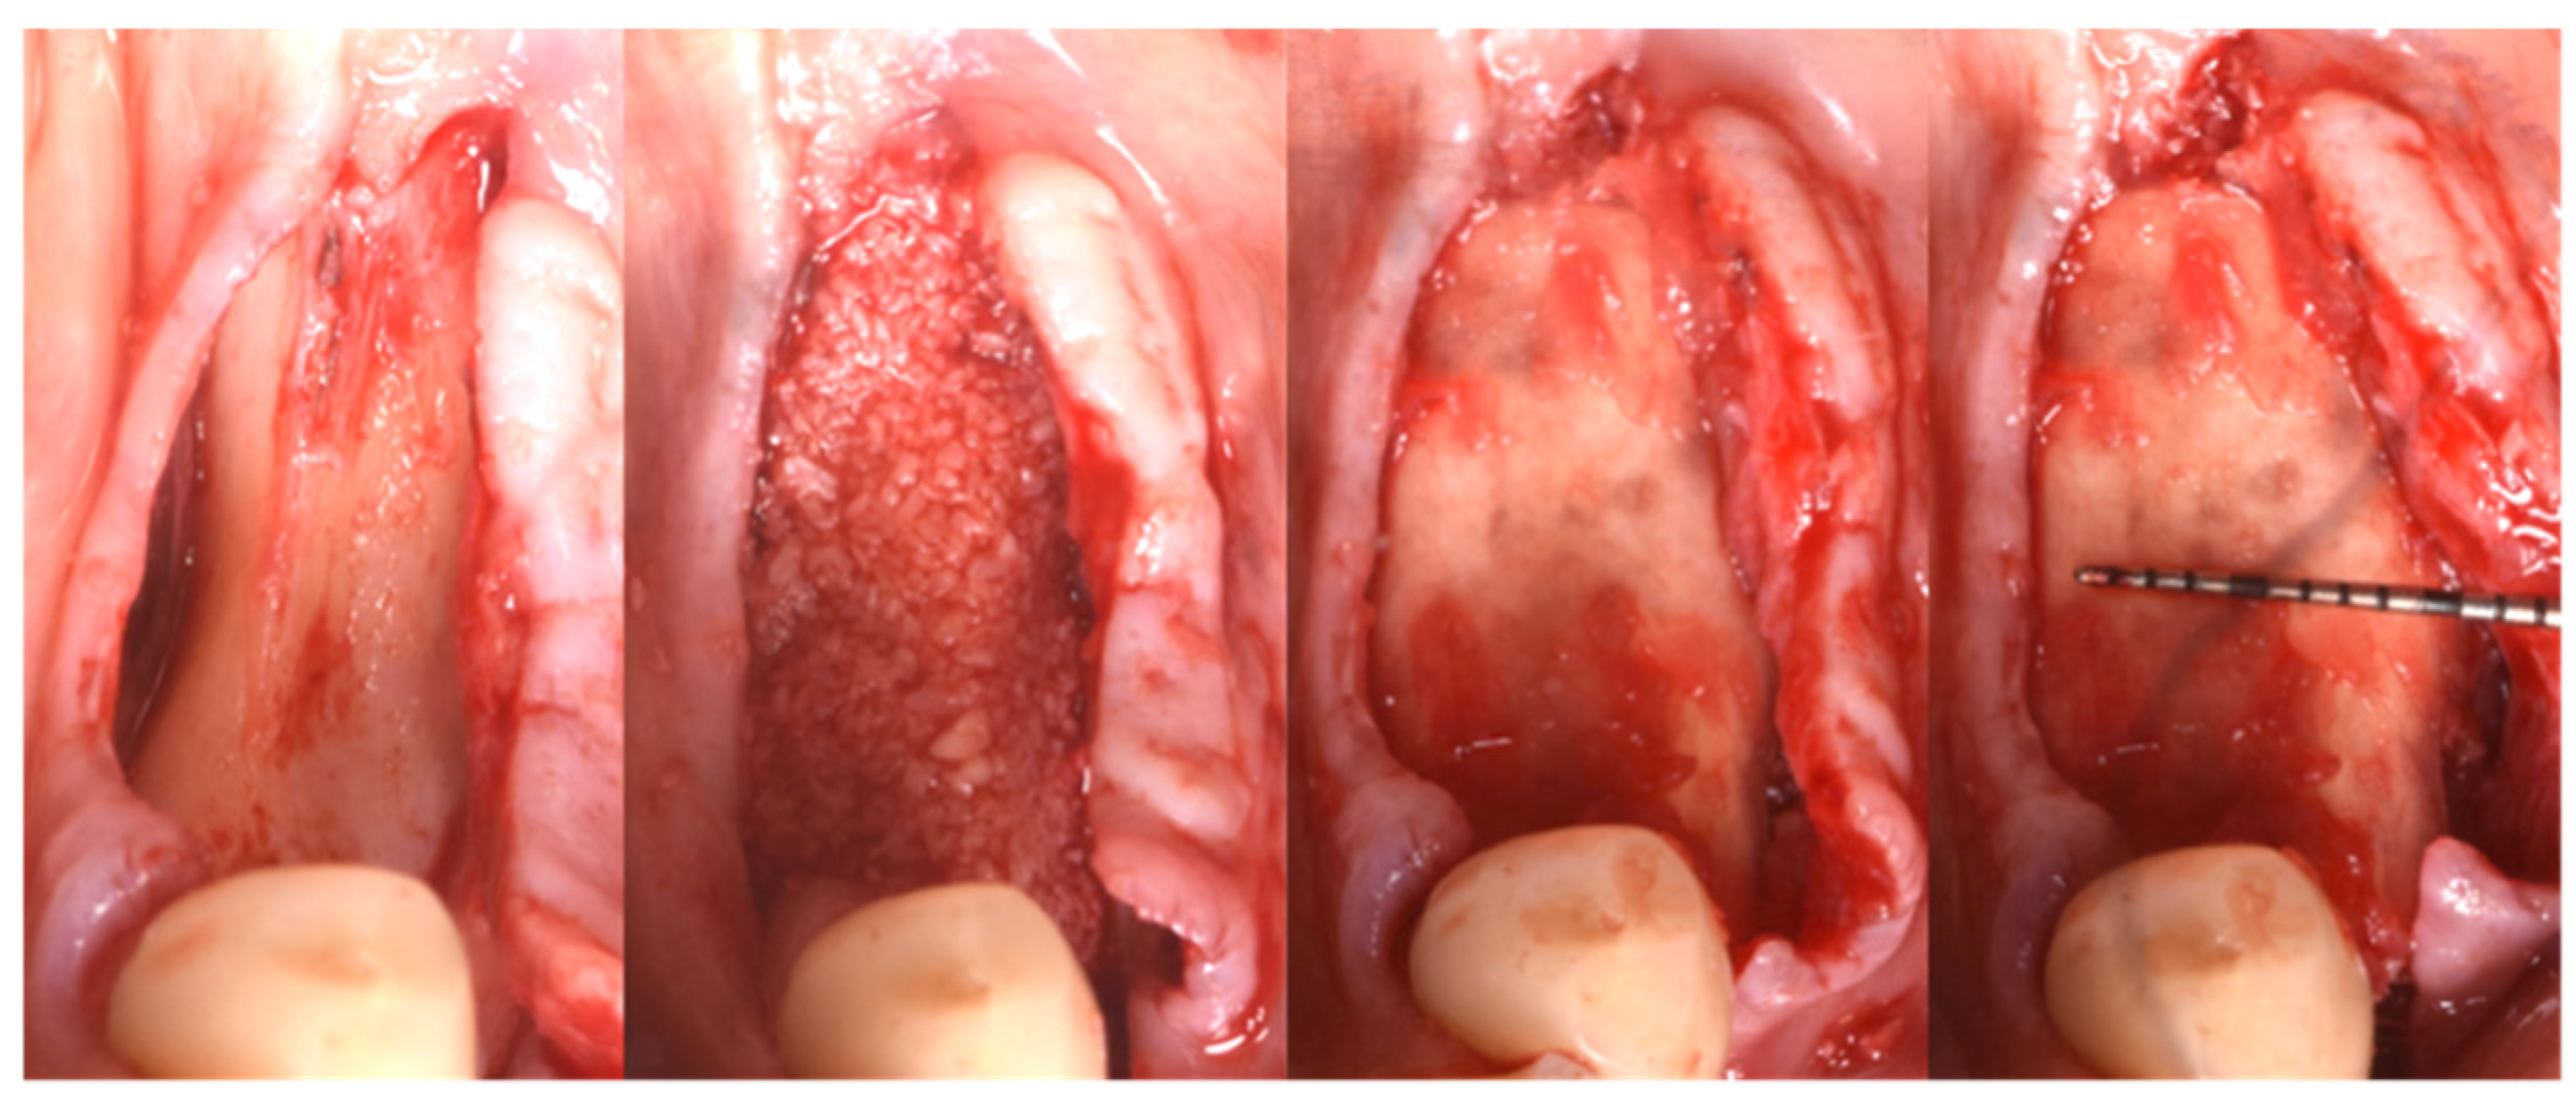

3.3. Hard Tissue Augmentation

| T2 | Guided Bone Regeneration (3 months) | GBR with Flex Cortical Sheet (Bioteck SpA, Arcugnano, Italy) |